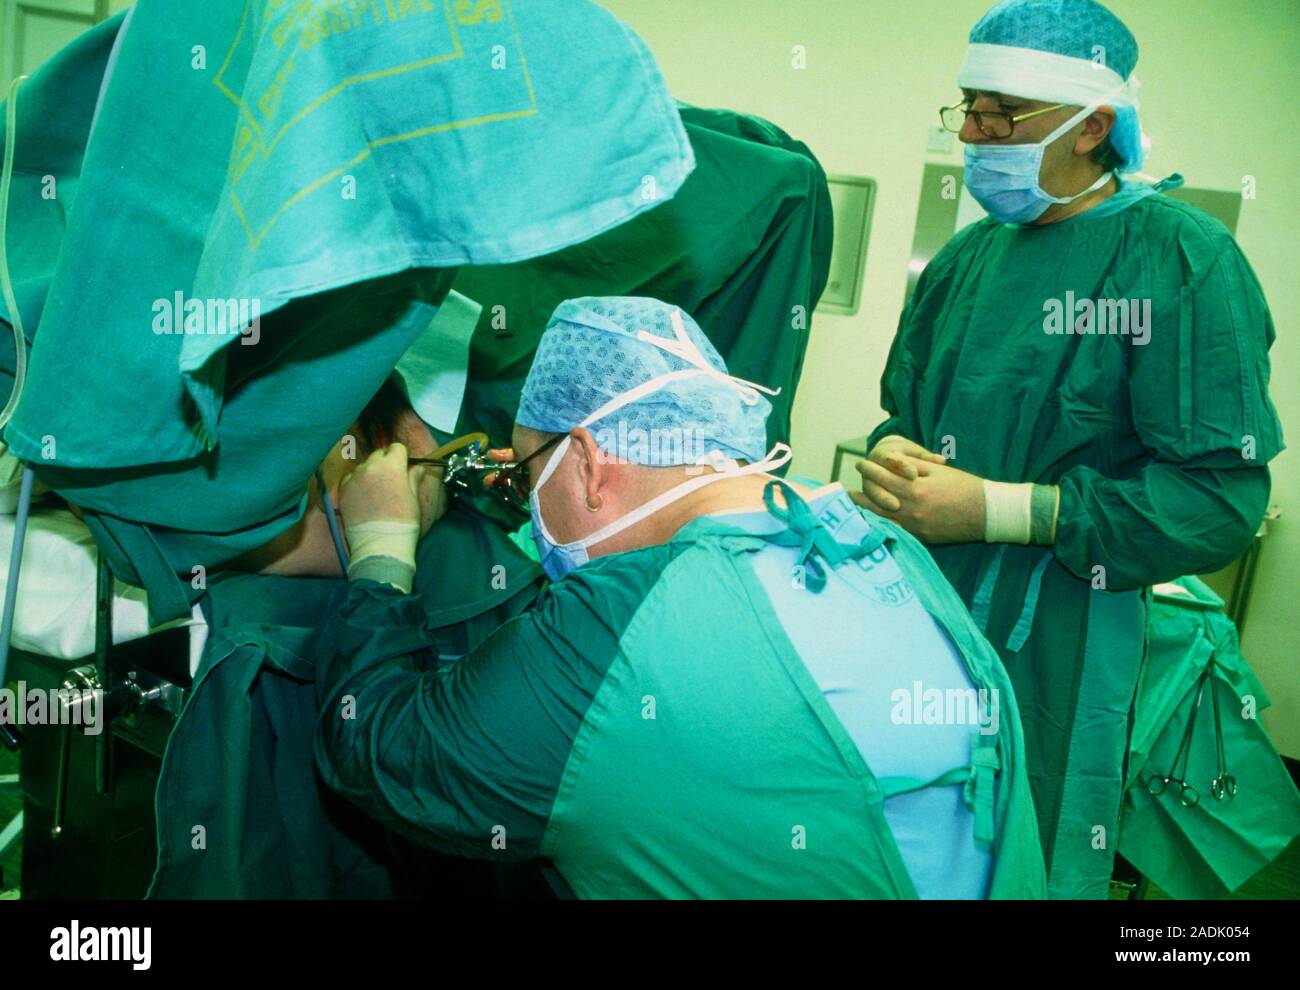

Современные методы лапаротомии и миомэктомии